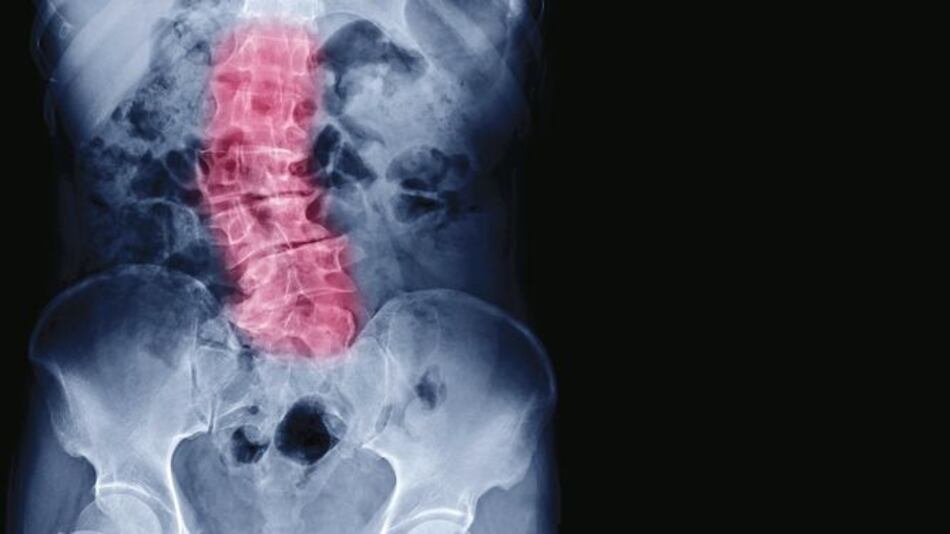

La osteoporosis es una enfermedad del esqueleto que afecta principalmente a los adultos mayores y los pone en riesgo de fracturas que podrían traer complicaciones mortales.

Al padecer de esta enfermedad, el hueso se torna más poroso y frágil y las personas se vuelven más propensas a las fracturas, resalta el especialista.